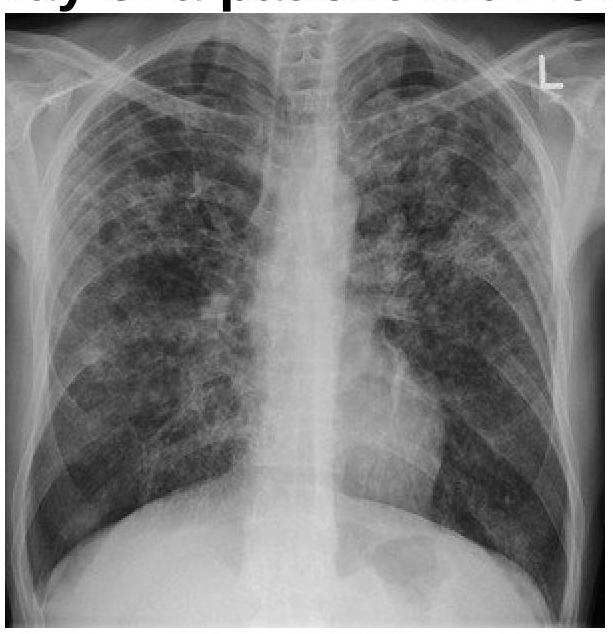

PA view of chest X-ray is given here. What is the diagnosis?

Explanation: ***Right Pneumothorax with left tracheal shift*** - The image shows a large **radiolucency (black area) on the right side** of the chest, indicative of **air in the pleural space**, consistent with a **right-sided pneumothorax**. - The **trachea is shifted towards the left** (away from the pneumothorax), which is the **expected finding** in pneumothorax due to increased pressure in the right pleural space pushing mediastinal structures to the contralateral side. - In pneumothorax, the trachea and mediastinum shift **away from** the affected side due to the pressure effect of air accumulation in the pleural cavity. - This **contralateral tracheal deviation** is a classic radiological sign of pneumothorax and helps confirm the diagnosis. *Right Pneumothorax with right tracheal shift* - While the **right pneumothorax** is correctly identified, the tracheal shift direction is incorrect. - In pneumothorax, the trachea shifts **away from** the affected side (contralateral), not toward it (ipsilateral). - **Ipsilateral tracheal shift** would suggest volume loss (atelectasis) or lung collapse, not pneumothorax alone. *Left Pneumothorax with right tracheal shift* - The pneumothorax is clearly on the **right side**, not the left. - The radiolucency and absent lung markings are visible on the right hemithorax. - A left pneumothorax would show these findings on the left side. *Left Pneumothorax with left tracheal shift* - There is **no pneumothorax on the left side** of the chest. - The left lung shows normal vascular markings and no evidence of pleural air. - This combination would be medically implausible as it suggests pneumothorax with ipsilateral shift.

Explanation: ***Miliary TB*** - The chest X-ray shows diffuse, small, uniformly distributed nodular opacities (2-3 mm in diameter) bilaterally, characteristic of "**millet seed**" pattern seen in **miliary tuberculosis**. - This pattern results from the hematogenous spread of *Mycobacterium tuberculosis* throughout the lungs, often presenting with **low-grade fever** and constitutional symptoms. *ILD* - **Interstitial lung disease (ILD)** typically shows reticular, nodular, or ground-glass opacities, sometimes with honeycombing, but the pattern is usually more heterogeneous and often basal or peripheral, unlike the uniform fine nodularity seen here. - While some ILDs can present with diffuse nodular patterns, the clinical context of **fever** and the classic "millet seed" appearance are more indicative of miliary TB. *Bronchopneumonia* - **Bronchopneumonia** presents as patchy, often ill-defined, multifocal areas of opacification or consolidation, usually distributed around the bronchi. - It does not typically cause the fine, diffuse, and uniform nodular pattern seen in this image, which represents widespread interstitial or alveolar involvement rather than primarily bronchial inflammation. *Consolidation* - **Consolidation** appears as a homogeneous opacification that obliterates vessels and airway walls, often with air bronchograms, typically confined to a lobe or segment. - The image shows diffuse nodular infiltrates rather than large, confluent areas of homogeneous opacification, making isolated consolidation an unlikely primary description.